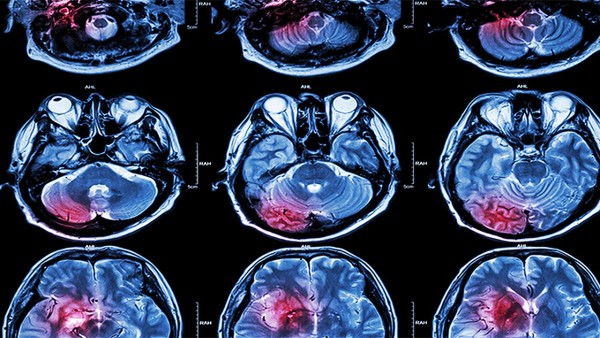

脑供血不足是指由于脑内某一部分血液供应不足造成的脑功能障碍。会出现头晕、头晕、头痛的症状,而且常伴有心烦、耳鸣、烦躁易怒、失眠多梦、记忆力减退、注意力不集中、健忘等症状。发现身体出现述症状时,我们应该及时院进行脑电图和脑CTA等检查,诊断脑供血不足,诊断脑供血不足时,应立即按医生指示进行治疗,严重可通过手术治疗恢复。除了进行药物和手术治疗外,在日常生活中还需要对脑供血不足进行保健护理,详细说明脑供血不足的保健护理。